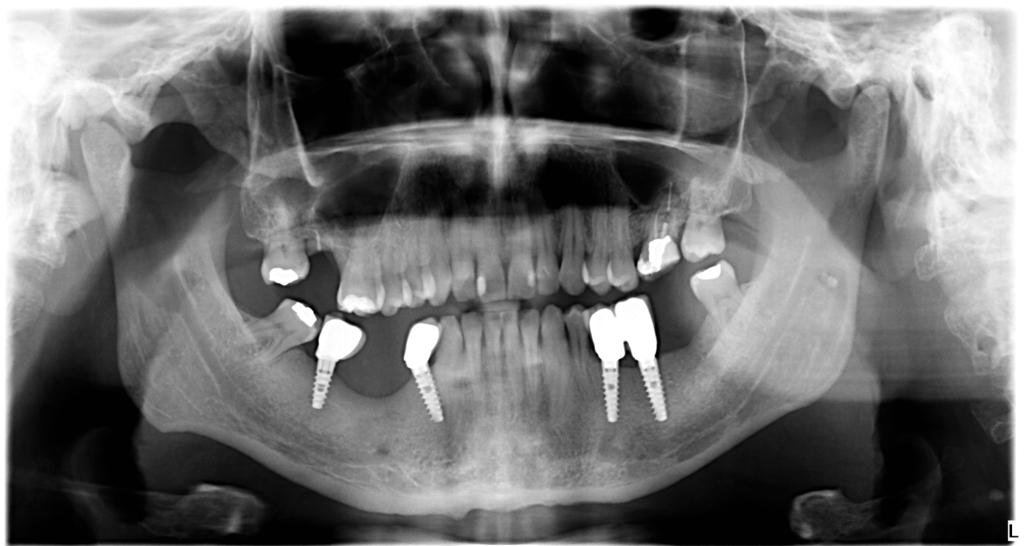

Me han derivado este pte y no se por donde comenzar. Agradeceria ayuda con la identificacion . Gracias!

Buscando Conexión y Compatibilidad de dos implantes.

Buenas tardes!! tengo un caso que necesito restaurar pero no logro identificar bien los implantes se que es una conexión octagonal pero no se con que sea compatible , los [...]